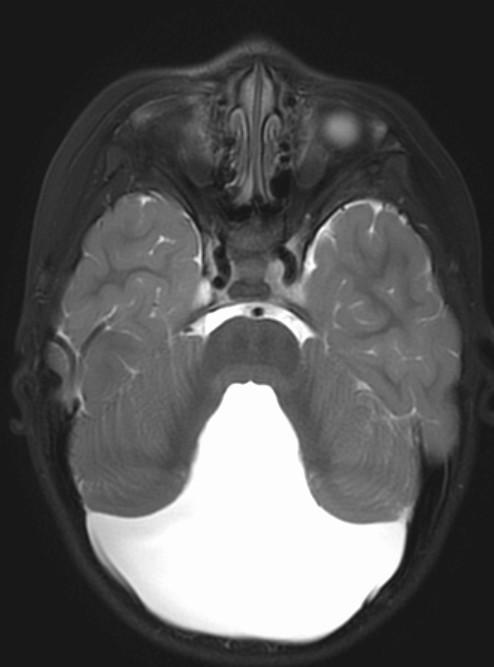

Differential for “cyst in the posterior fossa” starts with whether the vermis is normal or not.

Is the vermis normal? Can you identify the normal structures of the Vermis?

Malrotated hypoplastic vermis, with vertical primary fissure.

“OPEN” fastigial point of the fourth ventricle. Hypoplastic cerebellar hemispheres.

Enlarged posterior fossa

Cystic dilatation 4th ventricle

Uplifted tentorium, TSV sinus, torcula

“torcula-lambdoid inversion” with torcula above the lambdoid suture

Agenetic or hypogenetic vermis with “vermian tail, pushed upward

Cerebellar hypoplasia

CC anomalies 32%

Hydrocephalus up to 90%